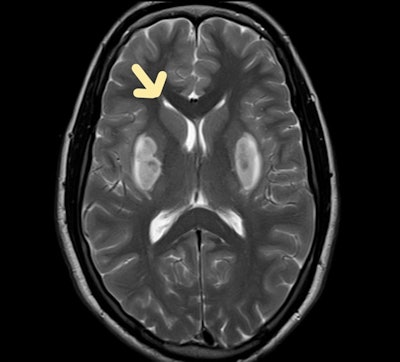

Methanol poisoning

Methanol is an extremely hazardous liquid that resembles ethanol in taste and smell. It is clear and colorless. It is an ingredient in a wide range of solvents that are sold commercially. Its intoxication can result from inadvertent or suicidal oral use of cleaning or antifreeze solutions, industrial solvents, or, on rare occasions, from wine or other alcoholic beverage adulteration, they noted.

Clinical manifestation varies and has a 12- to 24-hour latent period. Formaldehyde and formic acid are two hazardous byproducts of methyl alcohol metabolism that can cause a variety of clinical symptoms. Acute intoxication causes a severe metabolic acidosis that leads to severe neurological symptoms and sequelae.

"Most patients experience visual problems, such as blindness from optic nerve necrosis and demyelination, which lasts long after they recover. In the acute phase, neurological symptoms such as headaches, nausea, vomiting, dizziness, and altered sensorium are frequently experienced," they wrote.

Methanol poisoning. Bilateral putaminal hyperintensities are visible on T2-weighted axial MRI scan of the brain.

In these patients, CT shows hypoattenuation bilaterally in the putamen. MRI shows extensive subcortical white matter and basal ganglia abnormalities consistent with edema and bilateral putamen hemorrhagic changes.